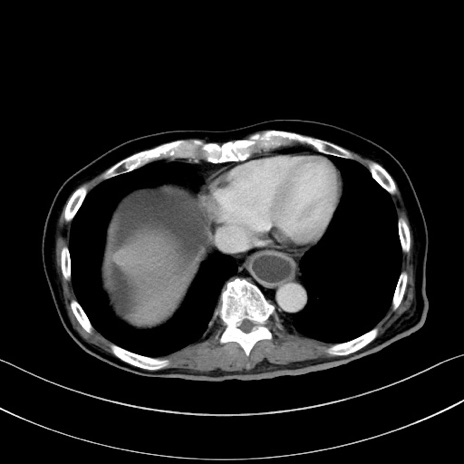

症例28(横断像)

【症例】60歳代男性

【主訴】嘔吐

【現病歴】胃癌にて胃全摘後。食思不振が悪化し、夜中に嘔吐することがある。

【既往歴】胃癌、胃全摘、脾摘、胆摘後

【データ】WBC 5900、CRP 10.56